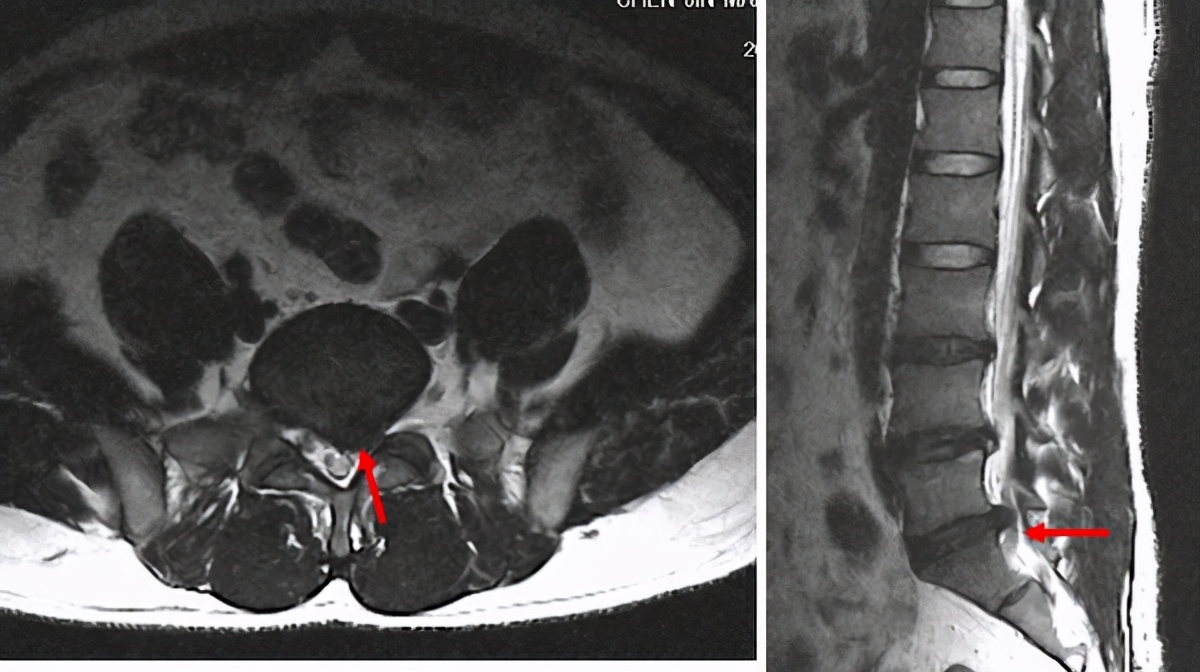

腰椎间盘突出通过CT和MRI(核磁共振)可以明确诊断,MRI没有辐射,并且能够观察得更细微,只是价格有点儿贵。